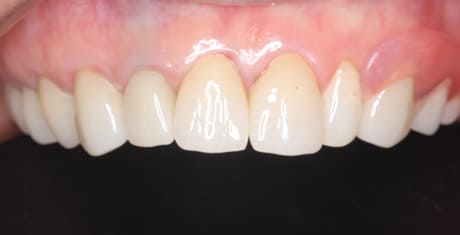

左奥1本は虫歯で抜歯となりました。

歯がないところには、インプラント、ブリッジ、入れ歯の3つが選択肢となりますが、インプラントには抵抗がおありで、ブリッジの土台の奥歯は歯周病のため、できるだけ負担をかけたくないとのことで、最終的に入れ歯をご希望されました。

見える外側は金属がないバネを用い、見えない内側は違和感が小さく強度に優れ、入れ歯が安定するチタンを用いた部分入れ歯(特殊なノンクラスプデンチャー)

入れ歯では、犬歯にバネがかかりますが「入れ歯と分からないように」とのご希望で、外側のバネは審美性が高く、内側には強度が高く安定性がよく、また違和感が少ないチタンを併用したノンクラスプデンチャーで治療を行いました。

左上に入れ歯を装着されていますが、金属のバネがなく自然な口元に